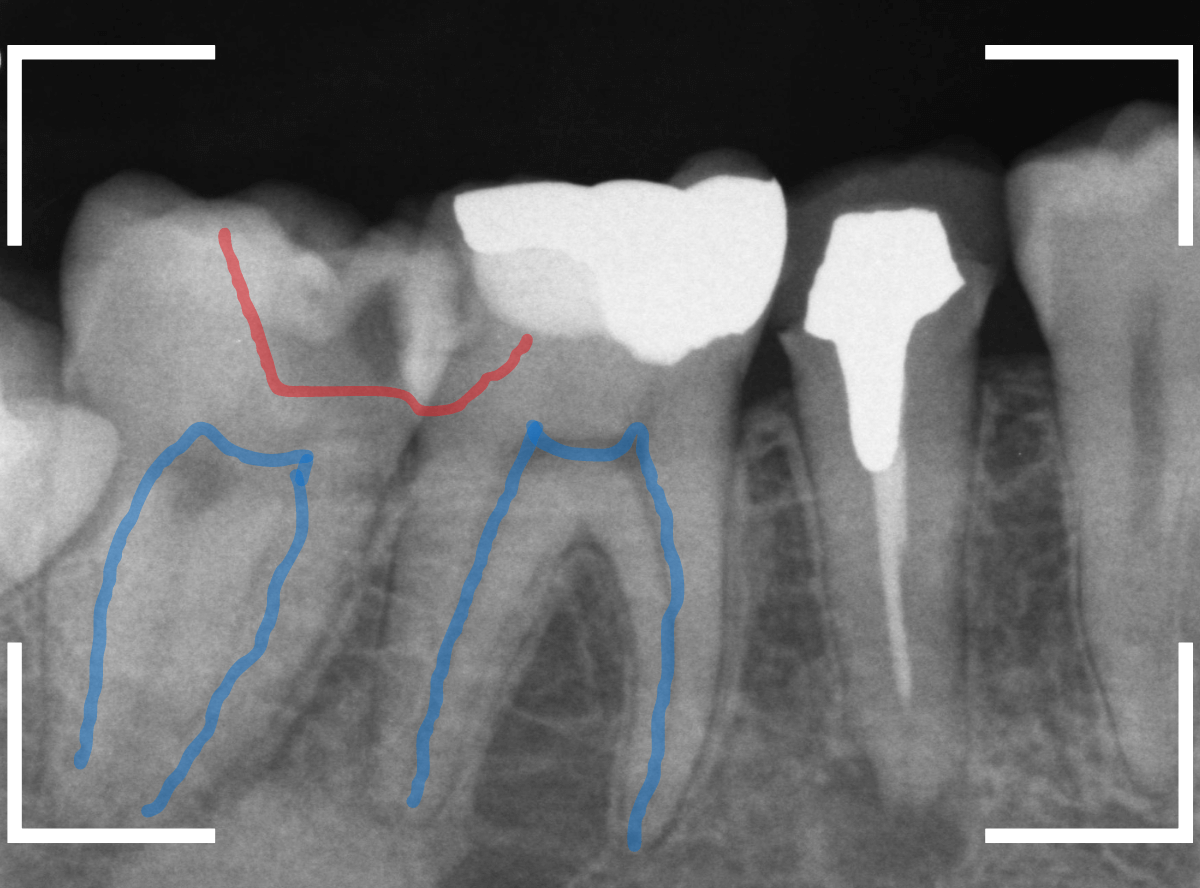

レントゲン写真で虫歯の状況を確認すると、赤い線のように虫歯になってるであろう事が予測できます。